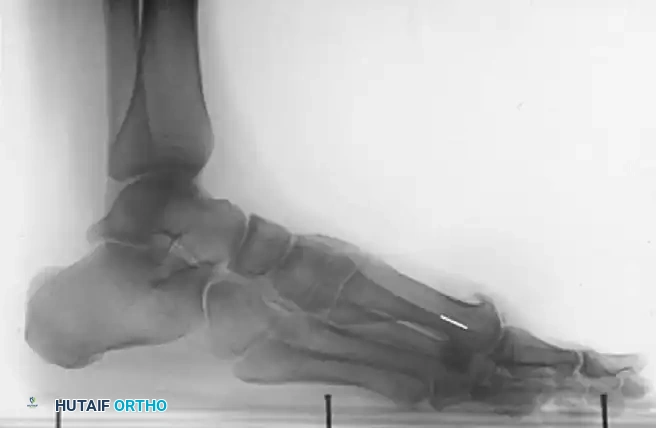

Post-op X-ray A

Post-op X-ray B

Post-op X-ray C

Figures 9-11: Immediate postoperative AP, Lateral, and Oblique radiographs demonstrating adequate dorsal metatarsal head resection and joint decompression.